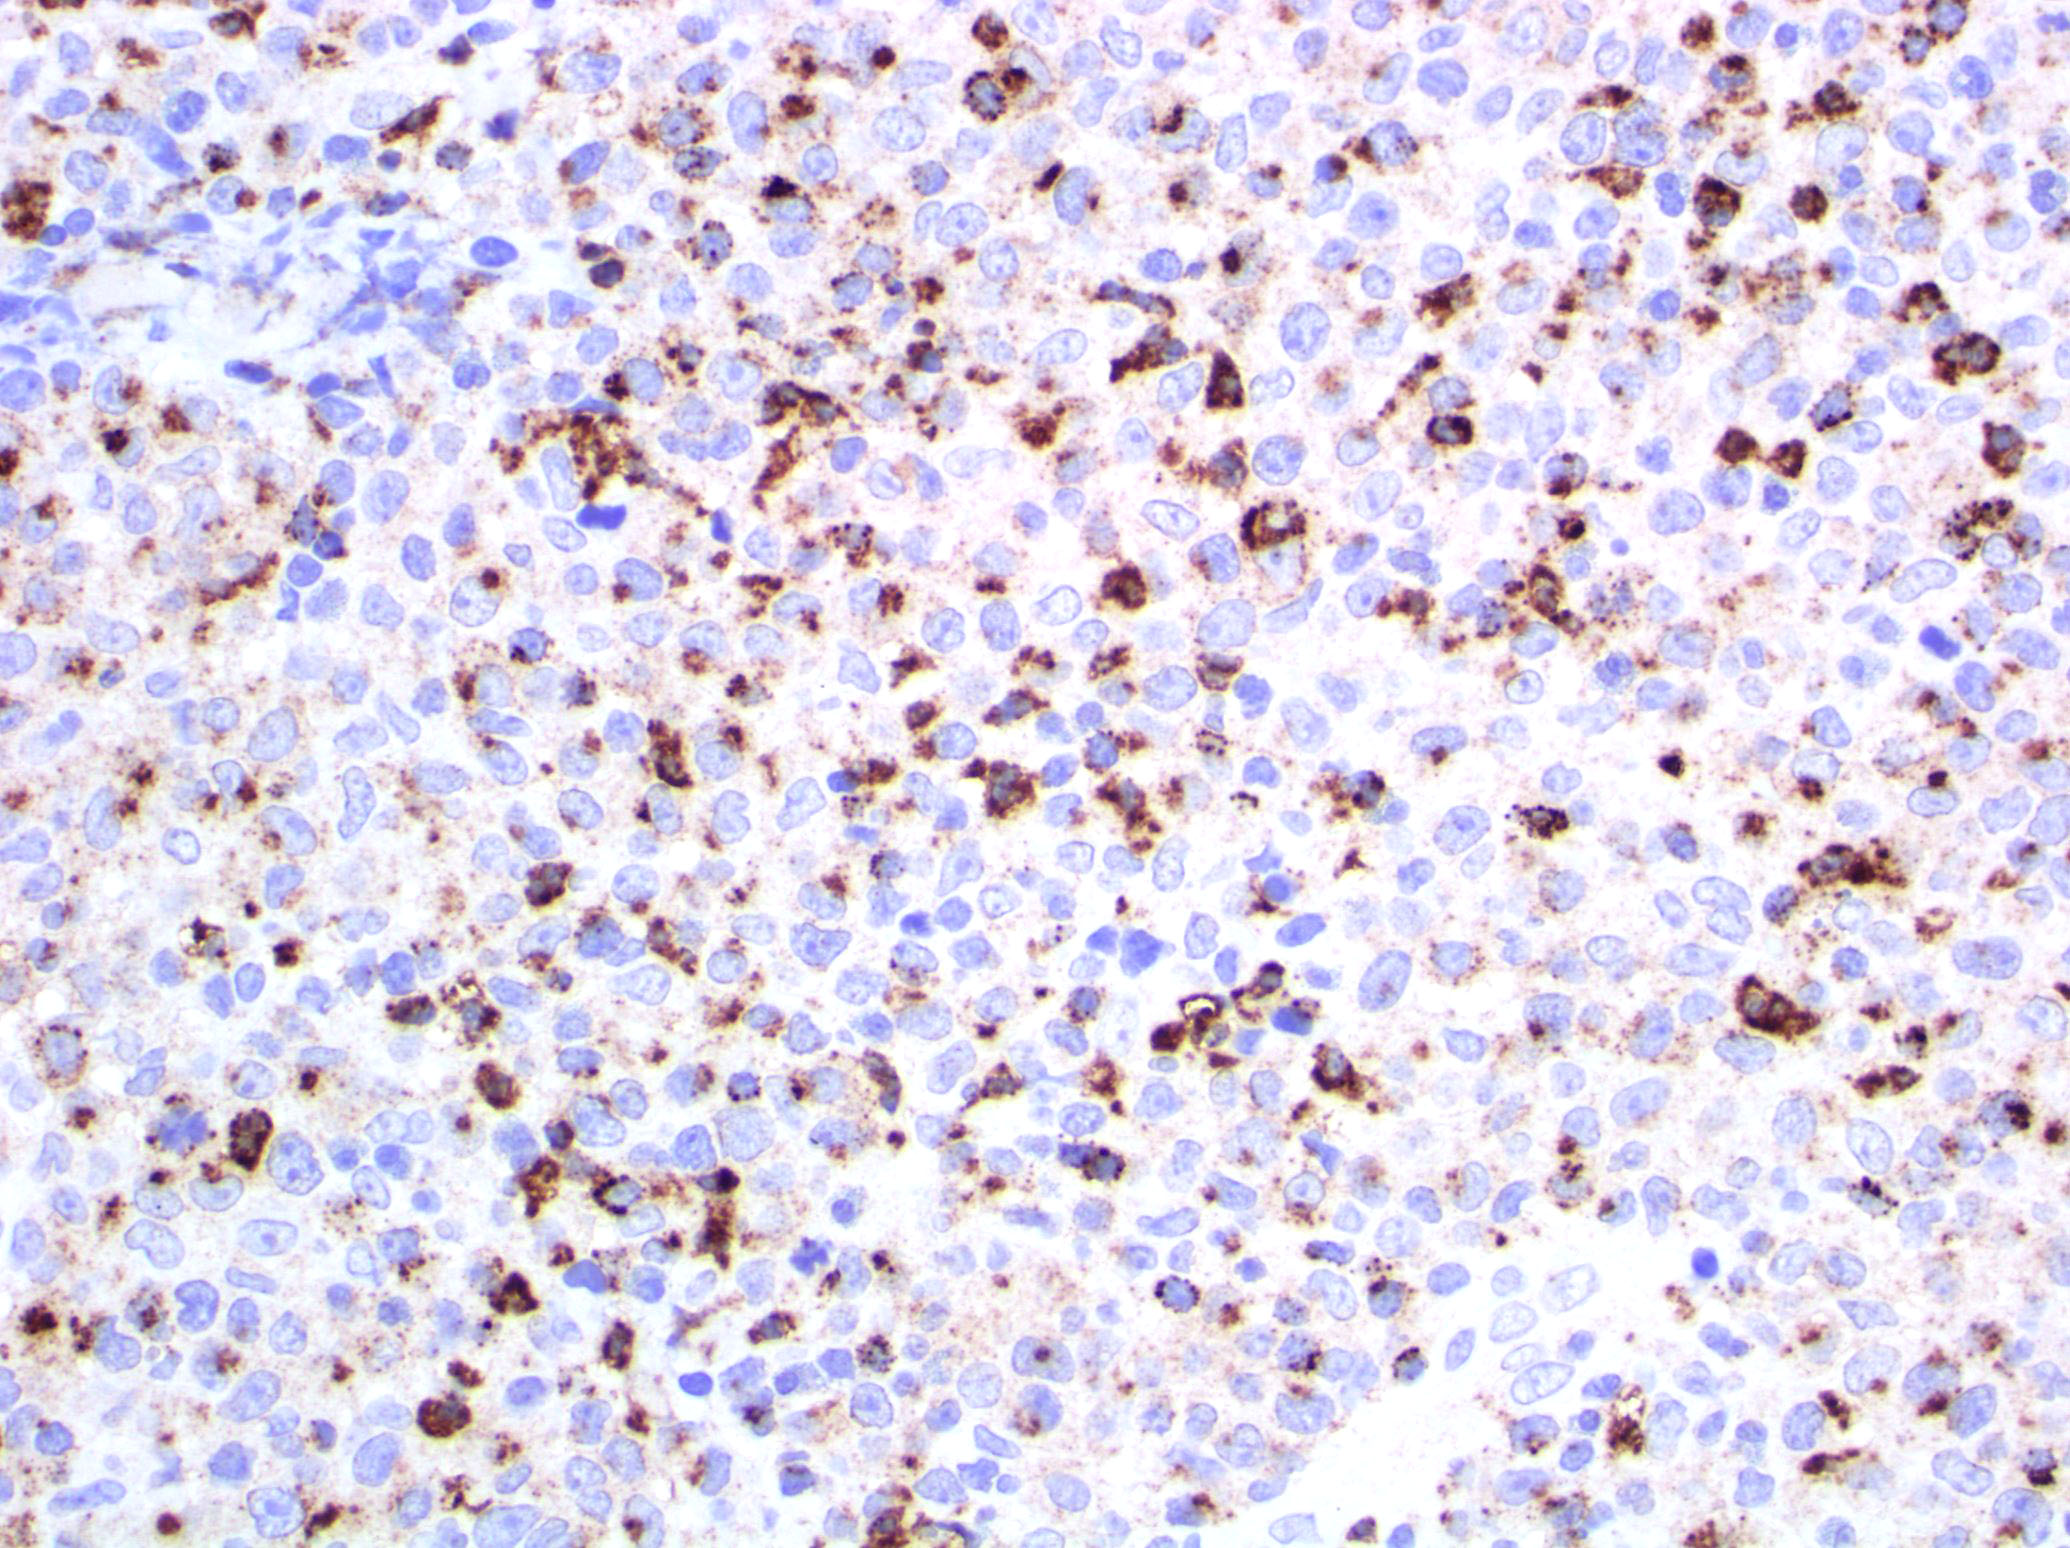

- Type D: atypical small to medium lymphoid infiltrate with epidermotropism; the neoplastic cells express CD30 and CD8 and mimic pagetoid reticulosis

Microscopic (histologic) images

Contributed by Roberto N. Miranda, M.D.